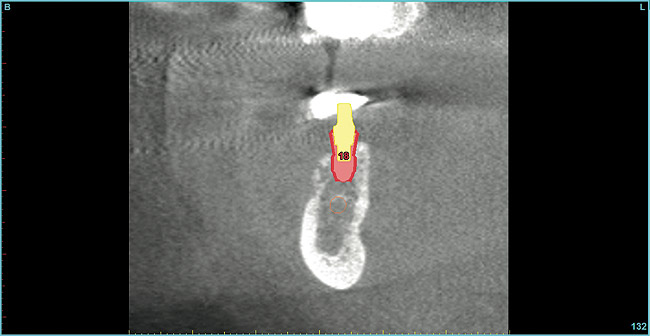

Not only does guided surgery result in safe and accurate implant placement, but by predetermining the path of implant insertion, the bone density of the osseous receptor site can be predetermined, which may affect the surgical procedure. In softer bone, clinicians will often under-prepare the osteotomy dimensions to increase the likelihood of achieving primary implant stabilization. Using Hounsfield units to estimate bone density, the surgeon can begin a surgical procedure with increased knowledge of the qualitative bone density prior to starting osteotomy preparation. Misch10 classified bone density by radiodensity numerical values to assist in approaching surgical implant placements. The bone density of each millimeter of osteotomy depth can be determined with planning software, giving the surgeon greater insight to the proposed implant bed (Figure 19). Turkyilmaz and McGlumphy11 found a clinical correlation between Hounsfield units measured on CT scans of proposed implant locations, insertion torque, and implant stability (ISQ). The radiodensity of sites of failed implants was consistently lower than those sites of successful implants. The authors concluded that a non-invasive method, such as CT scanning, may be used prior to implant surgery, and may allow clinicians to plan on modifying their approach before starting active therapy. Most implant planning software is capable of measuring bone density via Hounsfield units, which makes the realization of drill resistance prior to surgery a possibility for clinicians today.

Figure  19  Hounsfield units of each millimeter of proposed osteotomy calculated via planning software.

Figure 19